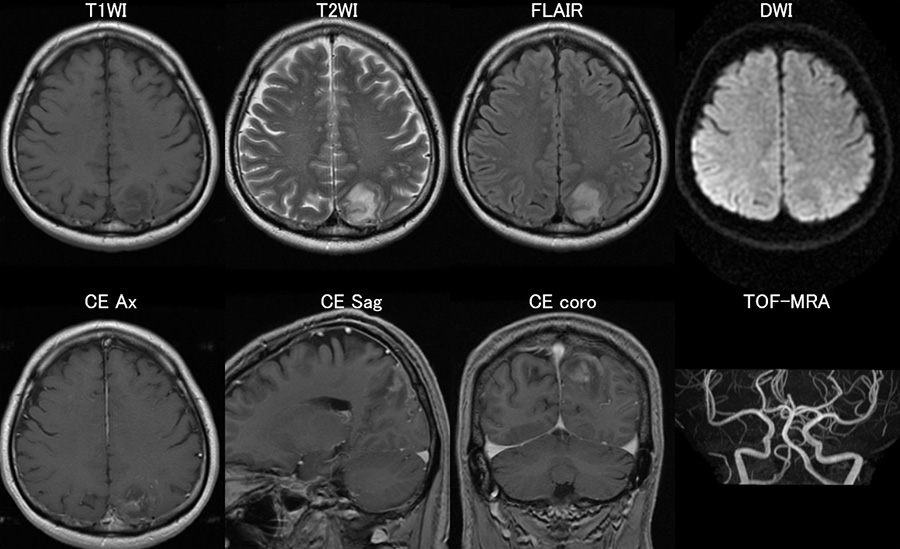

No.143症例3:50歳代 男性

【画像所見のまとめ】

• Key Images

• 左後頭葉皮質下白質の限局性T2延長、T1延長病変

• DWIでの異常信号はない→ADCは上昇

• focal swellingは軽度

• 皮質にそった軽度の増強効果

• CT,T2*WI(非掲示)を含め明らかな石灰化、出血性変化なし

• MRAで異常は認めない (病変部は撮影範囲外)